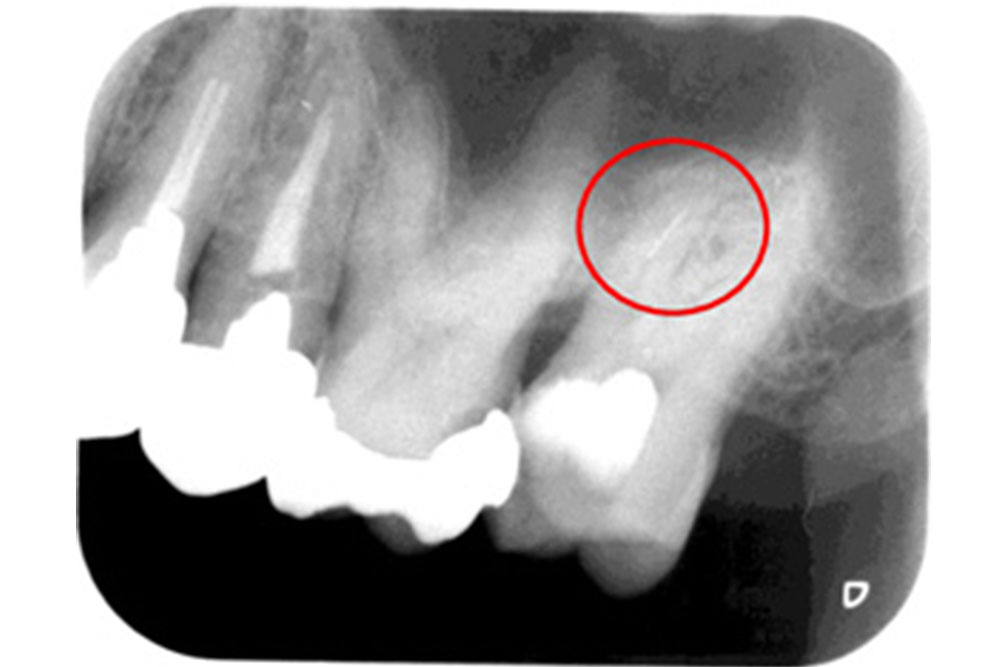

空洞に挟まったハリを除去することが可能

過去に他の医院で治療した際の折れたハリ(赤丸)が入っているレントゲン。

ハリを除去し、徹底的に洗浄したレントゲン。

空洞を根の先までしっかり埋めたレントゲン。

根の治療はハリを使用するため、ハリが折れて空洞の中に挟まってしまうケースがあります。これは治療の特性上、どうしても起こりうることなのですが、隙間を埋めることができずに空洞があると、しっかり洗浄されていないため、そこが痛み始めたらどうすることもできません。しかし、当院ではその根の中の細かい空洞に挟まったハリを除去し、治療することが可能です。ある患者様が半年以上もジンジンする痛みに悩まされ、いくつかの医院に行かれたそうですが治せる医院がなく、諦めかけていたそうです。しかし、当院にお越しいただいてハリを除去し治療を行ったところ、3回の通院のみで痛みを完全になくすことができました。